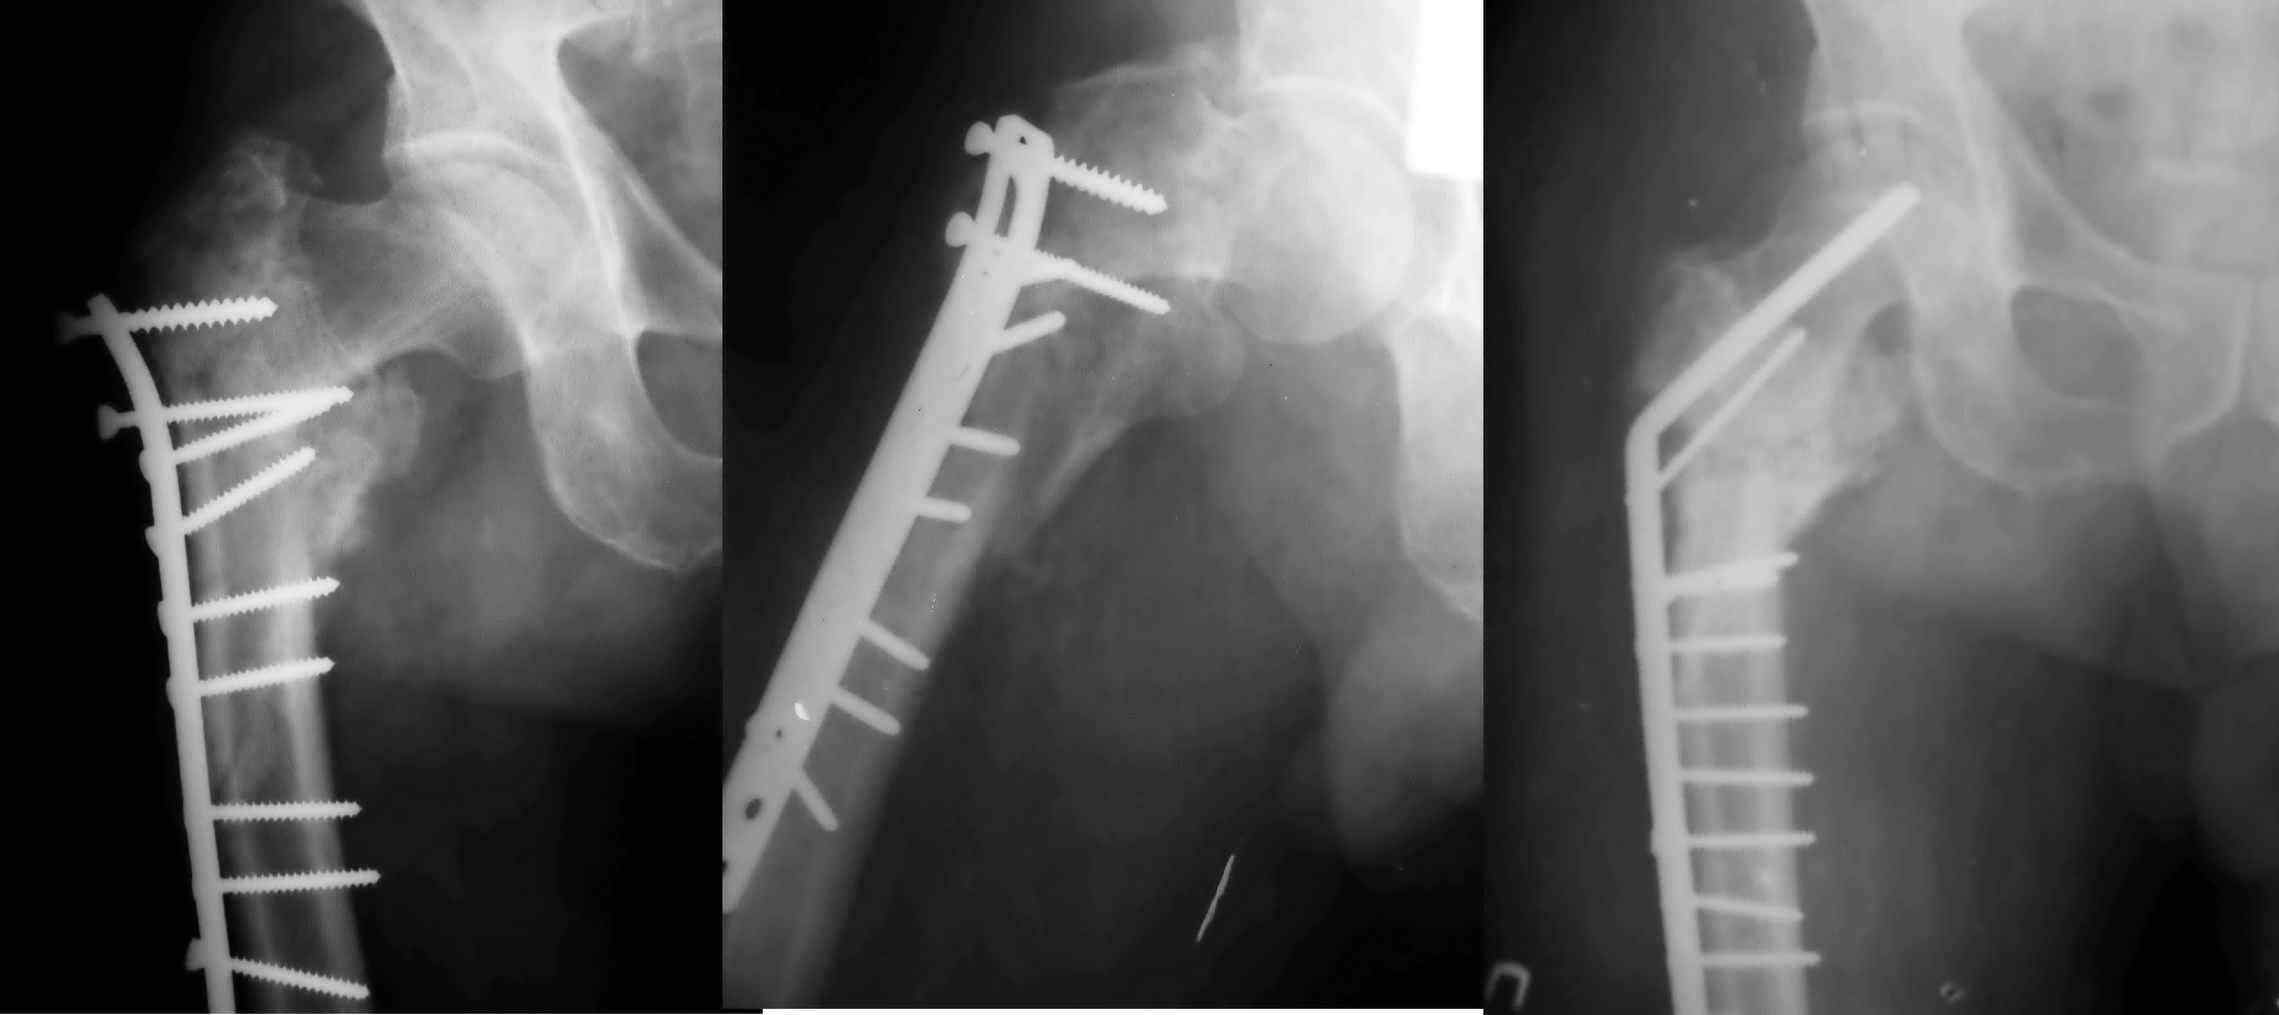

Уважаемый Глеб! Укорочение наверное побольше, да и наружно-ротационная установка скорее всего присутствует.  Суставная щель прекрасная, головка живее всех живых. Ратую за подвертельную  с латерализацией: исключает нарушение механической оси («исключает вальгус в коленe»), максимально удлиняет без натяжения m.iliacus. Для иллюстрации остеотомия-переделка (слава богу не автопеределка) у мужчины 65 лет.

PS. Извините за качество последнего снимка, рентгенограмма выполнена по м. жительства, там где  был проведен синтез. Последний снимок выполнен через 2 мес. п\о, больной без разрешения начал наступать, слава богу все обошлось.